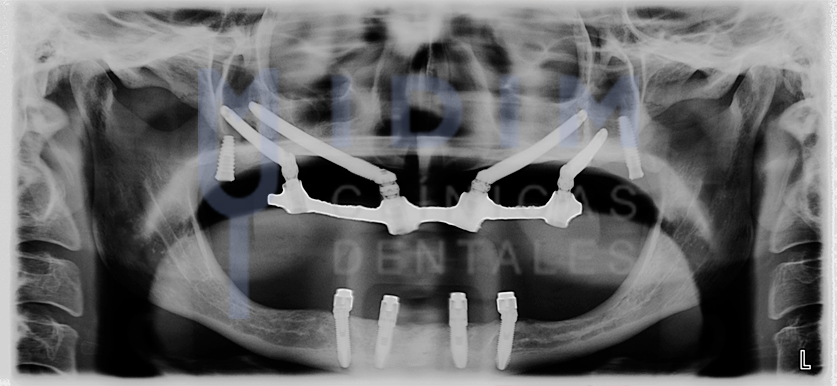

Los implantes cigomáticos son una solución avanzada en implantología dental diseñada para pacientes con una pérdida ósea severa en el maxilar superior. A diferencia de los implantes convencionales, estos implantes son más largos y están hechos de titanio para poder anclarse en el hueso cigomático, también conocido como hueso del pómulo o malar.

Este hueso, ubicado en la parte superior del rostro, ofrece una densidad y estabilidad excepcional, incluso en pacientes que han perdido todos sus dientes desde hace muchos años. Por ello, representa un punto de anclaje ideal para fijar los nuevos dientes sin necesidad de recurrir a injertos óseos.

En muchos casos, los implantes cigomáticos se combinan con 2 a 4 implantes convencionales más cortos colocados en la parte frontal del maxilar, siempre que haya suficiente hueso en esa zona. Y, sobre todos ellos se coloca una prótesis fija, devolviendo así la estética y función maxilar de forma inmediata al paciente.

Incluso en los casos más extremos, con ausencia total de hueso maxilar, es posible realizar el tratamiento con dos implantes cigomáticos por lado. Esto permite fijar una prótesis estable y funcional, ofreciendo hoy en día una solución duradera en situaciones que antes no tenían alternativa.